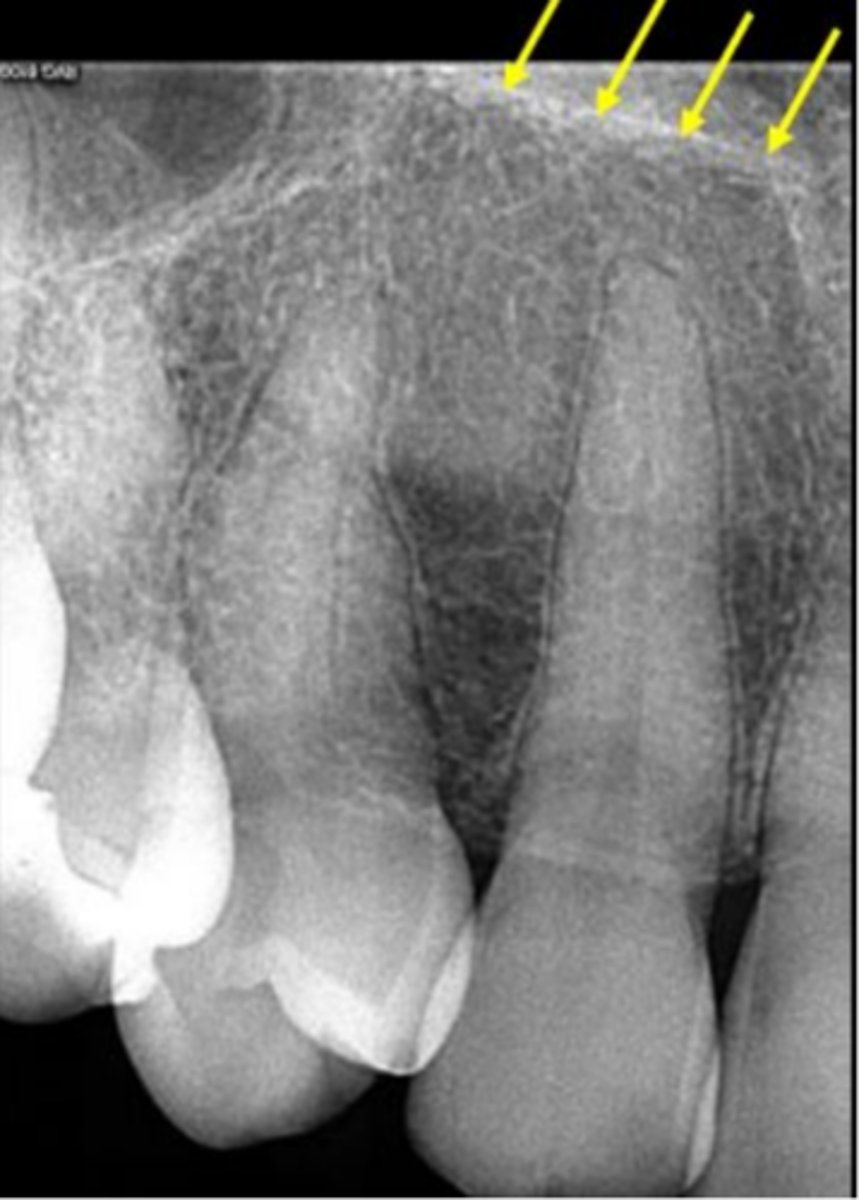

7

New cards

Floor of nasal cavity

What does the line indicated by the arrows represent?

<p>What does the line indicated by the arrows represent?</p>